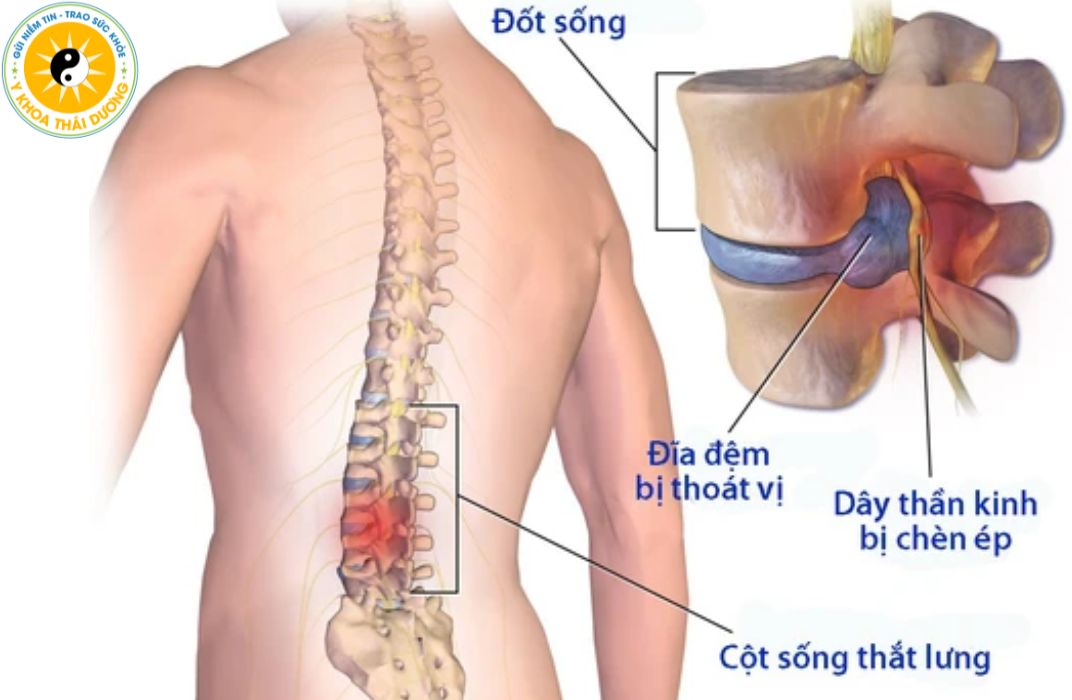

Thoát vị đĩa đệm có chữa dứt điểm được không?

Thoát vị đĩa đệm là một trong những bệnh lý cột sống phổ biến, đặc...